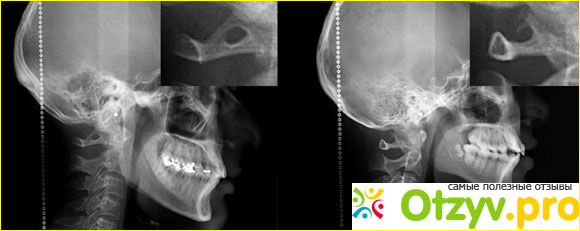

Аномалия Киммерле является анатомическим вариантом атланта - первый шейный позвонок. В частности, аномалию Киммерле следует рассматривать у людей, которые страдают головокружениями, головной болью, тошнотой и лицевой парестезией с болью в шее с необъяснимыми симптомами.

Окостенение боковой части задней атланто-затылочной мембраны имеет тенденцию охватывать позвоночную артерию в отверстии, ограниченном спереди суставной гранью С1, ниже по канавке для позвоночной артерии на верхней поверхности задней С1-арки и позади сама окостененная мембрана.

Это называют по-разному - ponticulus posticus (латинский для малого заднего моста), дугообразным отверстием, ретроартикулярным или ретрокондилярным отверстием, аномалиями Киммерле, отверстием сагиттального кольца или ретрондикальным позвоночным кольцом. Травственное исследование показало, что его заболеваемость составляет 13,8%.

Наличие этого отверстия связано с хроническими головными болями напряжения и сенсоневральной потерей слуха, а также болью в руках, болью в шее и головокружением. Такая проблема также является причиной рассечения позвонков и появления инсульта у детей из-за привязки позвоночной артерии внутри него. Данное отверстие можно легко идентифицировать на предоперационных рентгеновских лучах или парасагиттальных КТ-срезах, и тщательное изучение изображений важно для того, чтобы начать лечение во время. Сосудистые аномалии возникают, когда артерии, вены, капилляры или лимфатические сосуды не развиваются должным образом. Некоторые из них могут обезображивать, а некоторые могут представлять опасность для здоровья. Многие сосудистые аномалии врожденны (присутствуют при рождении), но другие могут развиваться позже в жизни ребенка.

Атлант это уникальный позвонок по своему строению. Данный позвонок не имеет тела, а состоит их дуг. В задней дуге данного позвонка есть углубление, и через него проходит нерв спинномозговой, а также артерия позвоночная. Если костные ткани, которые образую борозду на артерии спинномозговой разрастается очень сильно, то сама выемка в размере становится меньше. Киммерле представляет собой перерождение борозды на задней дуге атланта в канале или происходит углубление ее, которое возникает из-за того, что костная ткань растет не правильно.